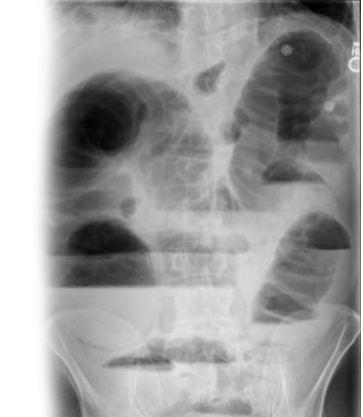

Обзорная рентгенография органов брюшной полости – важный метод исследования, который применяется для исключения проявлений острой хирургической патологии: кишечной непроходимости и свободного газа в брюшной полости. Эта неинвазивная диагностика позволяет получить информацию о состоянии органов брюшной полости, таких как желудок, кишечник, печень, желчный пузырь и поджелудочная железа.